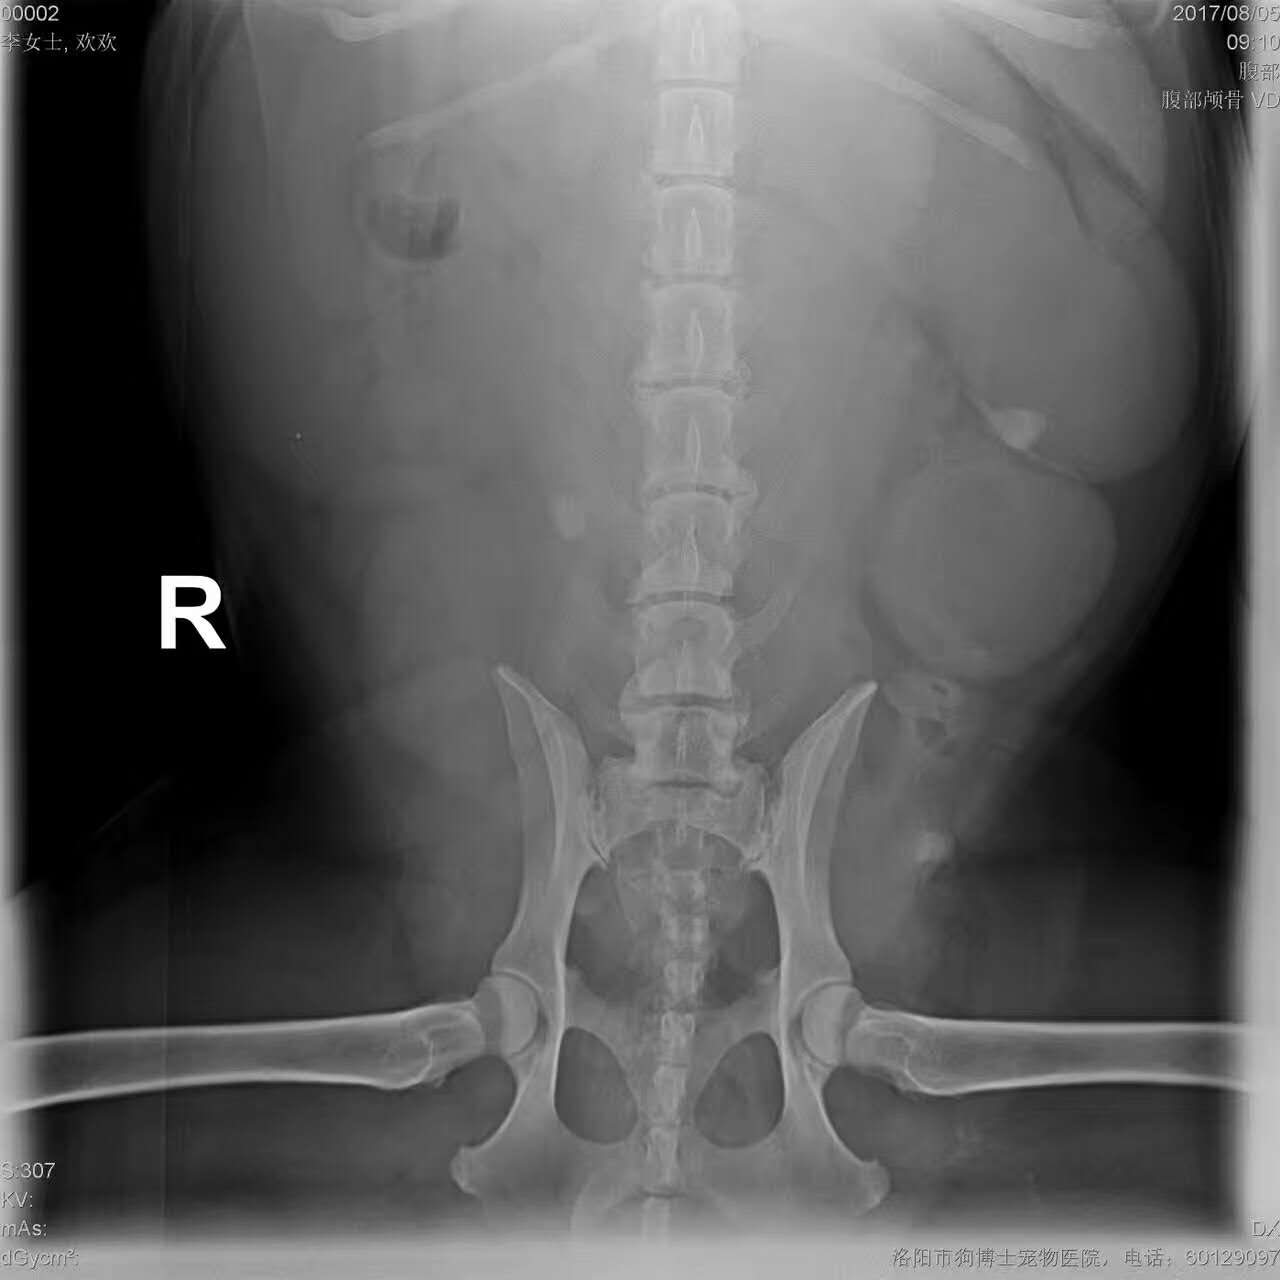

子宮蓄膿手術(shù)摘除:秋田犬,歡歡,9歲,母,未絕育,近期腹圍持續(xù)增大,昨日從***大量流出黃白色分泌物,主人懷疑即將分娩,來醫(yī)院檢查后,確診為子宮蓄膿,且高燒40.2度,病情危急,遂實施子宮卵巢摘除術(shù),手術(shù)順利。PS:再次提醒,不以繁育為目的的養(yǎng)寵,應(yīng)盡早絕育,能大大降低子宮蓄膿、乳腺腫瘤、卵巢囊腫等病的發(fā)病率,洛陽狗博仕寵物醫(yī)院。